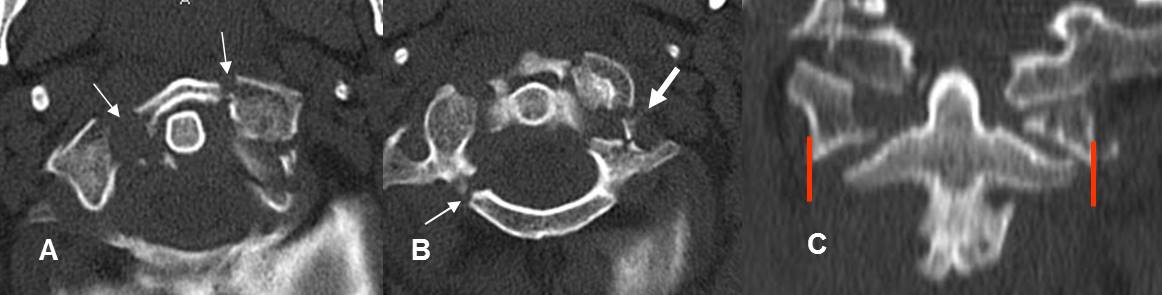

Fig 190. Fractura de Jefferson.

A y B: TAC axial. Fractura conminuta del arco anterior y de la parte derecha del arco posterior de C1. Existen fragmentos libres dentro del canal y compromiso del agujero vertebral en el lado izquierdo. (Flecha gruesa).

C: TAC reconstrucción coronal. Desalineación entre las masas laterales de C1 y C2.